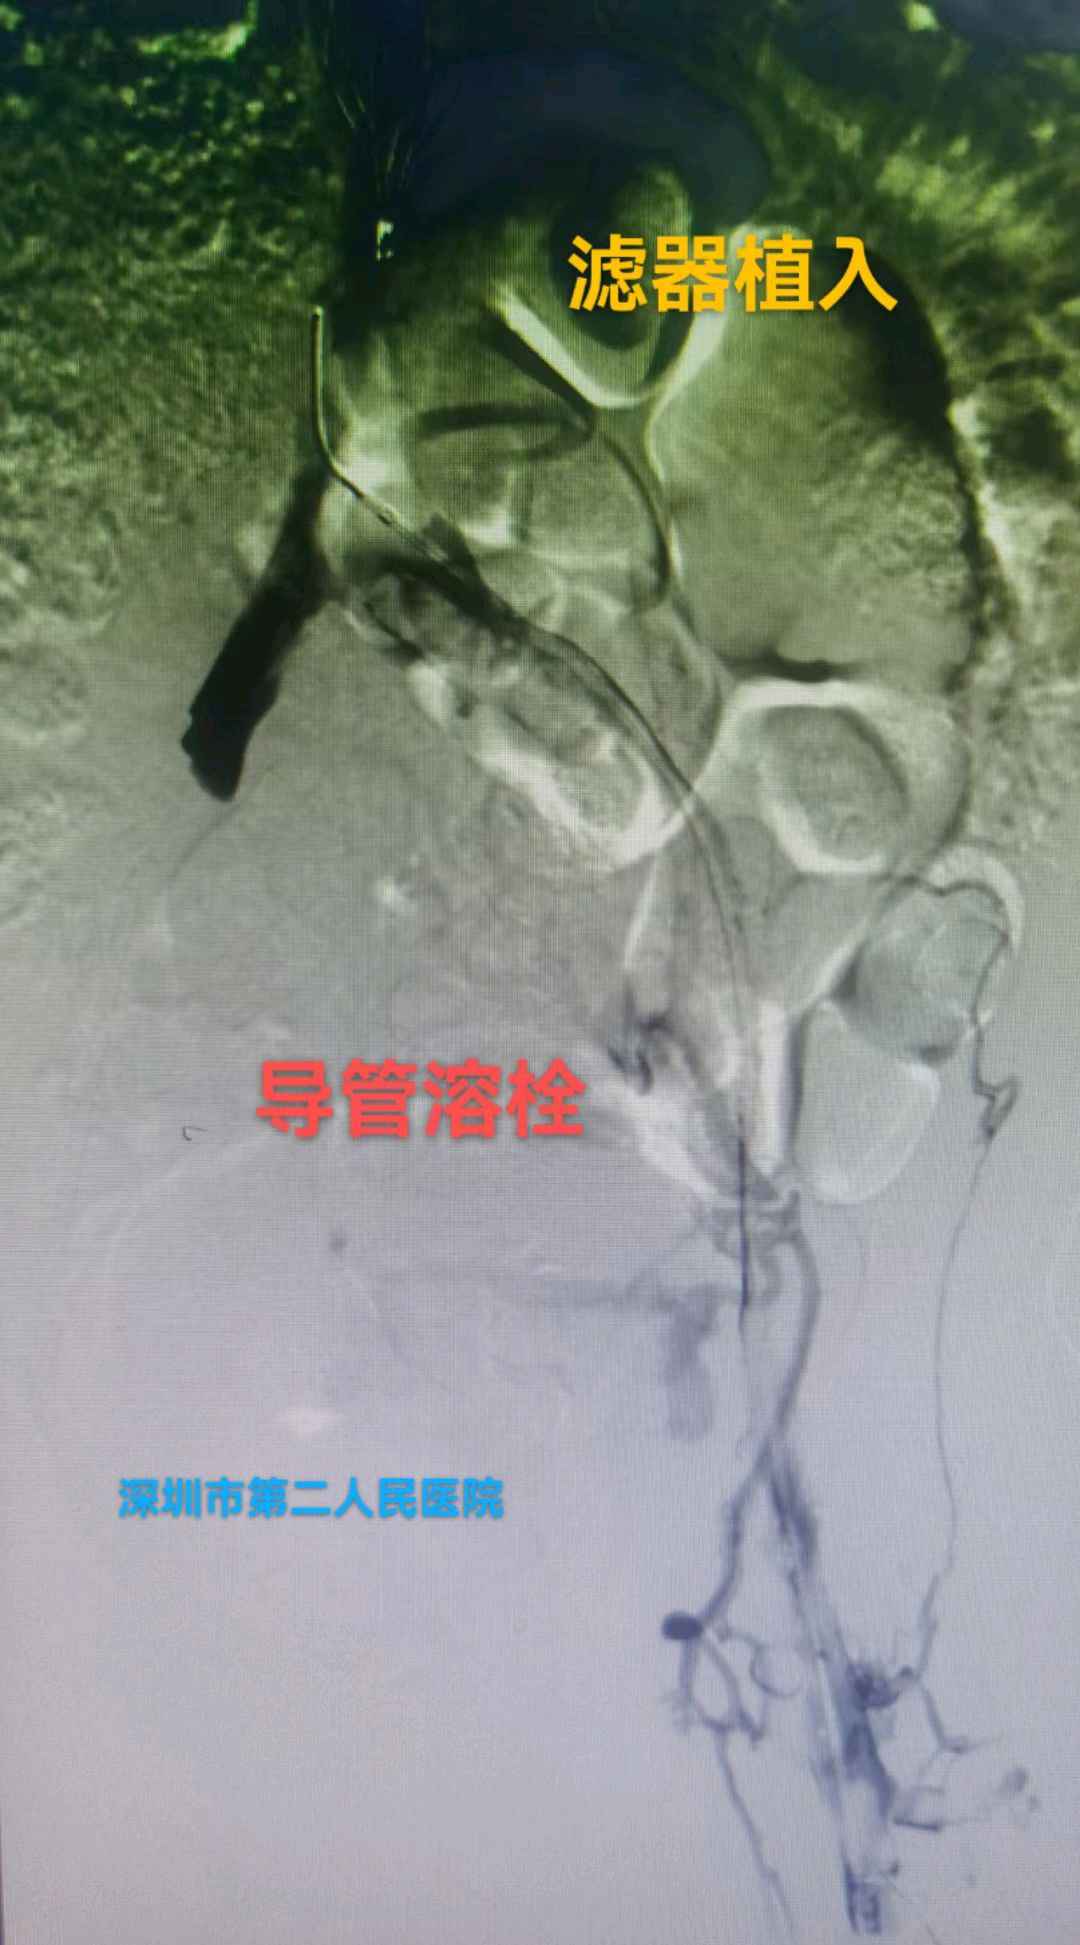

答:首先需要做的就是看医生;然后避免挤压、按摩、揉搓患肢,可用专科垫枕抬高患肢。主要治疗方式为:抗凝、溶栓、外科手术、介入手术等。

答:这个就需要根据患者自身情况制定个性化治疗策略,主要策略为:①保守抗凝治疗:②系统溶栓治疗;③导管接触性溶栓治疗;④机械性血栓清除治疗;⑤必要时球囊扩张和支架植入治疗;⑥急危重症病人需切开取栓治疗等。